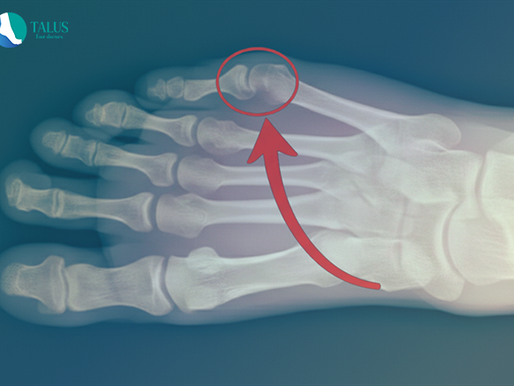

(IV) El juanete de sastre: la causa oculta del dolor en tu meñique que casi nadie conoce

El juanete de sastre o quintus varus provoca dolor en el borde externo del pie. Descubre sus causas, síntomas y los tratamientos más efectivos para aliviarlo, prevenir su avance y recuperar tu bienestar.